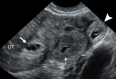

The Society of Radiologists in Ultrasound convened a multisociety panel to develop a first-trimester US lexicon based on scientific evidence, societal guidelines, and expert consensus that would be appropriate for imagers, clinicians, and patients. Through a modified Delphi process with consensus of at least 80%, agreement was reached for preferred terms, synonyms, and terms to avoid. An intrauterine pregnancy (IUP) is defined as a pregnancy implanted in a normal location within the uterus. In contrast, an ectopic pregnancy (EP) is any pregnancy implanted in an abnormal location, whether extrauterine or intrauterine, thus categorizing cesarean scar implantations as EPs. The term pregnancy of unknown location is used in the setting of a pregnant patient without evidence of a definite or probable IUP or EP at transvaginal US. Since cardiac development is a gradual process and cardiac chambers are not fully formed in the first trimester, the term cardiac activity is recommended in lieu of 'heart motion' or 'heartbeat.' The terms 'living' and 'viable' should also be avoided in the first trimester. 'Pregnancy failure' is replaced by early pregnancy loss (EPL). When paired with various modifiers, EPL is used to describe a pregnancy in the first trimester that may or will not progress, is in the process of expulsion, or has either incompletely or completely passed. © RSNA and Elsevier, 2024 Supplemental material is available for this article. This article is a simultaneous joint publication in Radiology and American Journal of Obstetrics & Gynecology. All rights reserved. The articles are identical except for minor stylistic and spelling differences in keeping with each journal's style. Either version may be used in citing this article. See also the editorial by Scoutt and Norton in this issue.